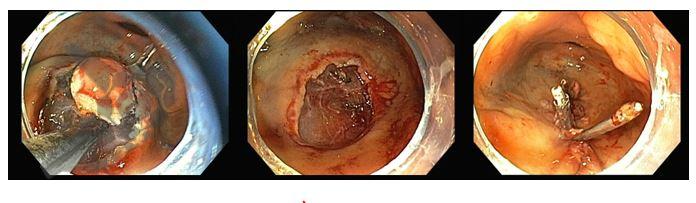

Realizado tratamento endoscópico pela técnica de ESD híbrida (Fig. 2)